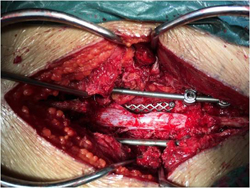

图3-7,后路肿瘤切除照片显示肿瘤切除后T12,L1至L4,L5椎弓根螺钉固定,L1-3椎体间钛网植入,左侧L2神经根切除。

图3-8,术后标本,标本CT平扫与术前图像对比,显示整块肿瘤切除的范围,切除边界充分。

图3-9,术后X片及CT显示肿瘤切除后内固定重建。

术后病理证实:高分化软骨肉瘤。病人术后左侧髂腰肌肌力减弱,其余下肢肌力5级;术后7天下地活动,可走平路。术后3个月复查时左下肢肌力基本正常,病人可正常行走。术后随访33个月,肿瘤无复发,内固定稳定。